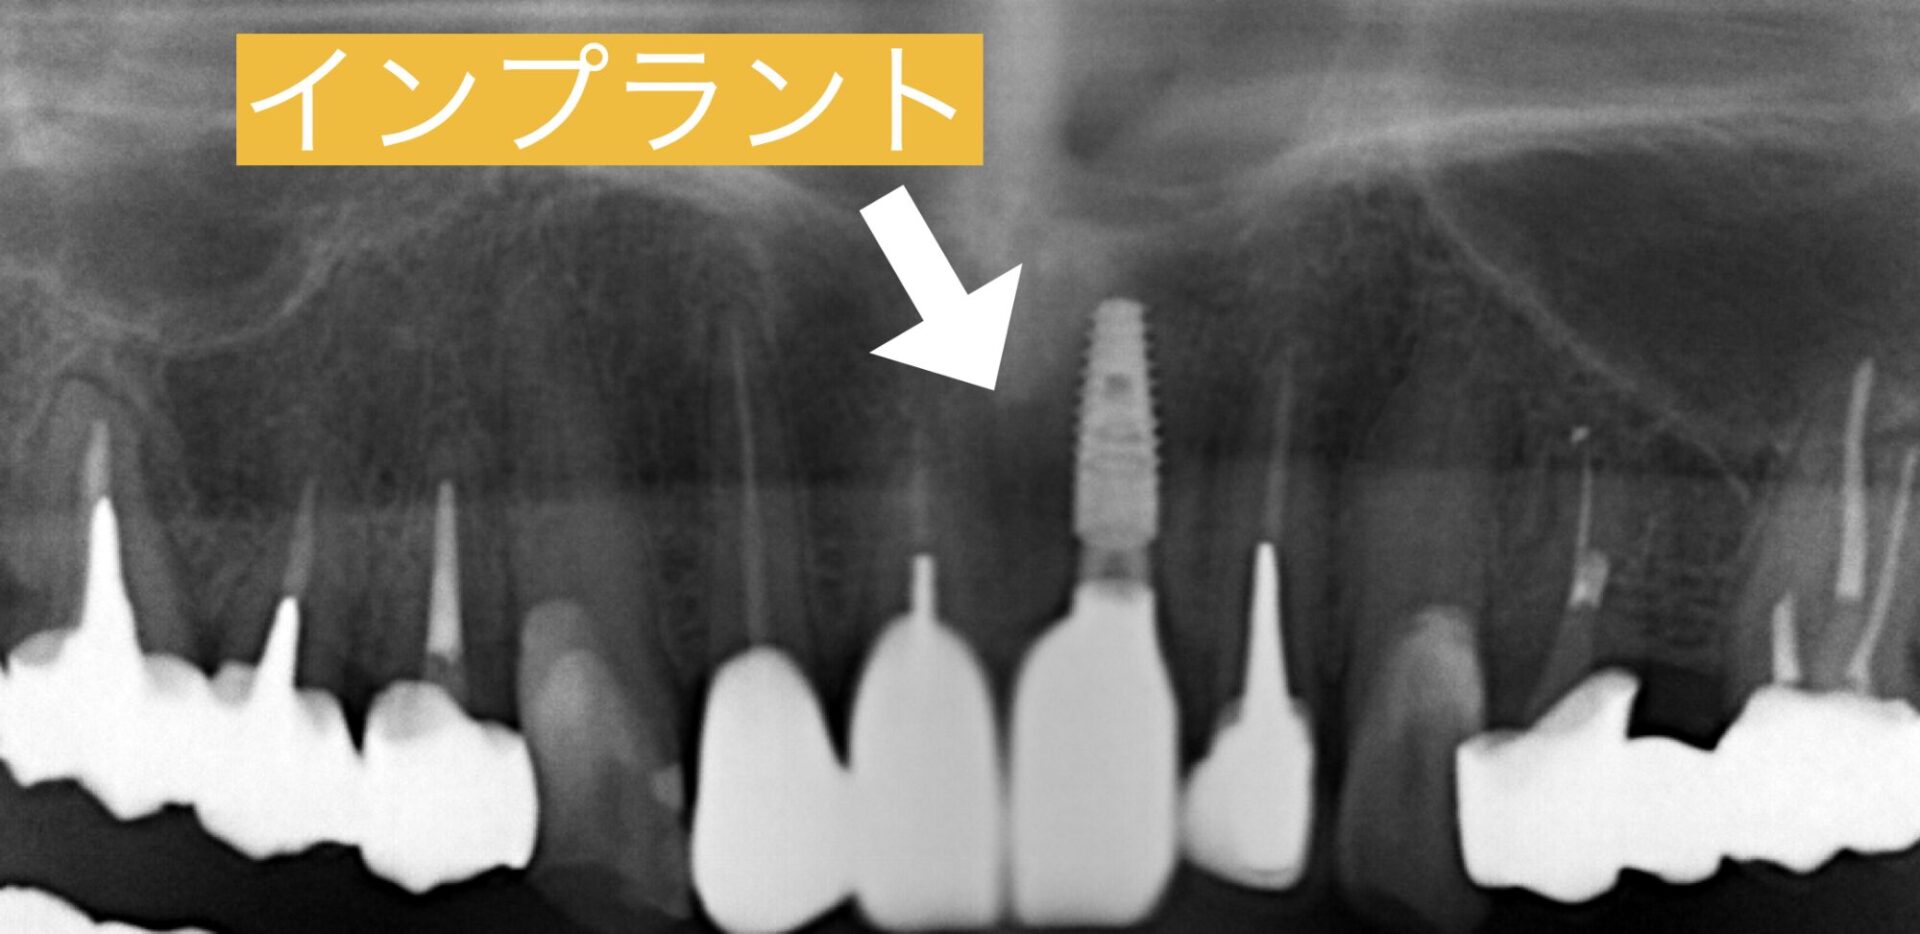

口腔外科で埋伏歯を摘出後しCT撮影を行なったところ、埋伏歯を抜くために骨がかなり削除されており、しばらく治癒を待つことになりました。4ヶ月ほどで傷の治りと骨が安定的に治っていく治癒過程が見られたのでインプラント埋入を行いました。

インプラント手術は抜歯即時埋入を行いました。埋伏歯は抜歯されていますが、今回の歯折した歯を抜き、そのままインプラントを埋入しました。抜歯即時埋入はほとんど痛みがなく抜歯したその日にインプラントが入ります。手術が1回ですみ患者様にも喜んでいただけました。